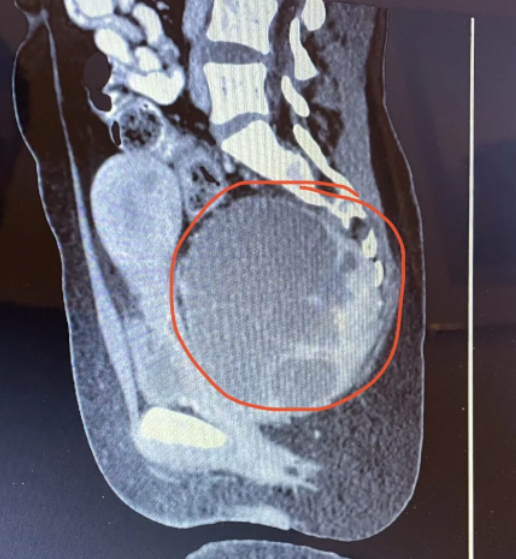

Exame emergencial identificou o gigante tumor na mulher – Foto: Kennedy News/The Sun/Reprodução/NDExame emergencial identificou o gigante tumor na mulher – Foto: Kennedy News/The Sun/Reprodução/ND

Exames de emergência constataram então que ela possuía um raro tumor de células gigantes com quase 14 centímetros.